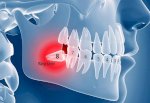

Răng Khôn Là Gì ? Có Nên Nhổ Răng Khôn Không ?

Bị Áp Xe Răng Khôn Có Nguy Hiểm Không? Điều Trị Thế Nào?

Nhổ Răng Khôn Không Đau

Độ Tuổi Mọc Răng Khôn Là Khi Nào?

Có Nên Nhổ Răng Khôn Hàm Trên Không?

Nhổ Răng Khôn An Toàn Ở Vũng Tàu